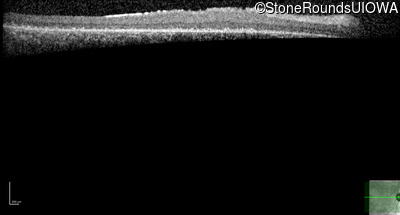

Optical Coherence Tomography - Right - 20/125 +1 sc

Exemplar / OCT Stack

OCT Stack